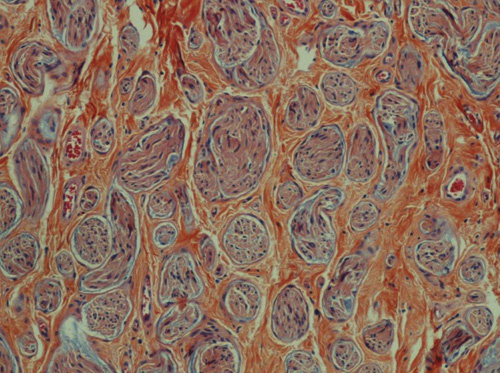

Ved kirurgisk eksplorasjon fant vi en hvitlig, relativt velavgrenset tumor som utgikk fra eller var adherent til en struktur vi oppfattet som restene av klitoris. Tumor var 1,5 cm stor og ble ekstirpert. Histologisk undersøkelse viste traumatisk nevrom (fig 1). Det postoperative forløpet var ukomplisert. Senere har kvinnen hatt en viss grad av vedvarende ømhet i området, men uten at det har vært mulig å påvise residiv av tumor ved palpasjon, ultralyd- eller MR-undersøkelse. Hun kan gjennomføre samleie uten smerte.

Traumatisk nevrom er ikke en egentlig neoplasme, det representerer en nervesvulst som oppstår pga. atypisk proliferasjon av regenererende nervefibre som følge av nerveskade. Traumatisk nevrom kan oppstå i alle organer der nerver skades. Malign transformasjon er ikke beskrevet. Kun fire tilfeller av traumatisk nevrom i vulva er tidligere publisert: ett som komplikasjon etter omskjæring (6), ett etter traume mot labium minus (17) og to i episiotomiarr (18, 19).